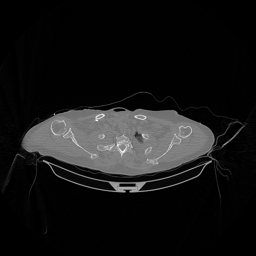

The results for simulated noisy data are shown in Fig. 2. The first and third rows display two representative slices from the test set, and the second and fourth rows present the corresponding error maps. The traditional WCE method suppresses cupping artifacts and recovers some missing anatomical structures but still shows noticeable deviations from the ground truth. Predictions from the four diffusion-based models demonstrate a markedly improved ability to restore anatomical structures. Among them, cDDPM fails to fully reconstruct the patient bed and retains residual noise in its outputs. This noise is attributable to an incomplete reverse denoising process rather than residual Poisson noise, as evidenced in our noise-free experiments (Fig. 5 in the Appendix). PatchDiffusion, diffusionGAN, and I2SB achieve similar visual quality, with I2SB producing the cleanest and most consistent reconstructions.

The experimental results on clinical head data are shown in Fig. 4. The reference images were reconstructed using the fast iterative shrinkage-thresholding algorithm (FISTA) with total variation regularization from non-truncated projection data. In the WCE reconstructions (Fig. 4(b)), severe truncation prevents accurate recovery of anatomical structures outside the FOV. Despite being trained solely on simulated data with a domain gap, all deep learning models can restore a substantial portion of the missing anatomy. Among them, the diffusion-based methods recover soft-tissue boundaries more faithfully than the conventional deep learning approach FBPConvNet, highlighting their stronger image generation capability. However, cDDPM reconstructions exhibit more noticeable noise than those from other methods, consistent with the simulated data results. The patchDiffusion model introduces artifacts within the FOV, likely due to its patch-wise processing strategy. While I2SB shares the same limitations as other diffusion models in perfectly restoring soft-tissue detail, it produces fewer residual noise patterns and fewer artifacts within the FOV boundaries. Overall, Fig. 4 demonstrates the strong efficacy of I2SB in reconstructing real CBCT data.